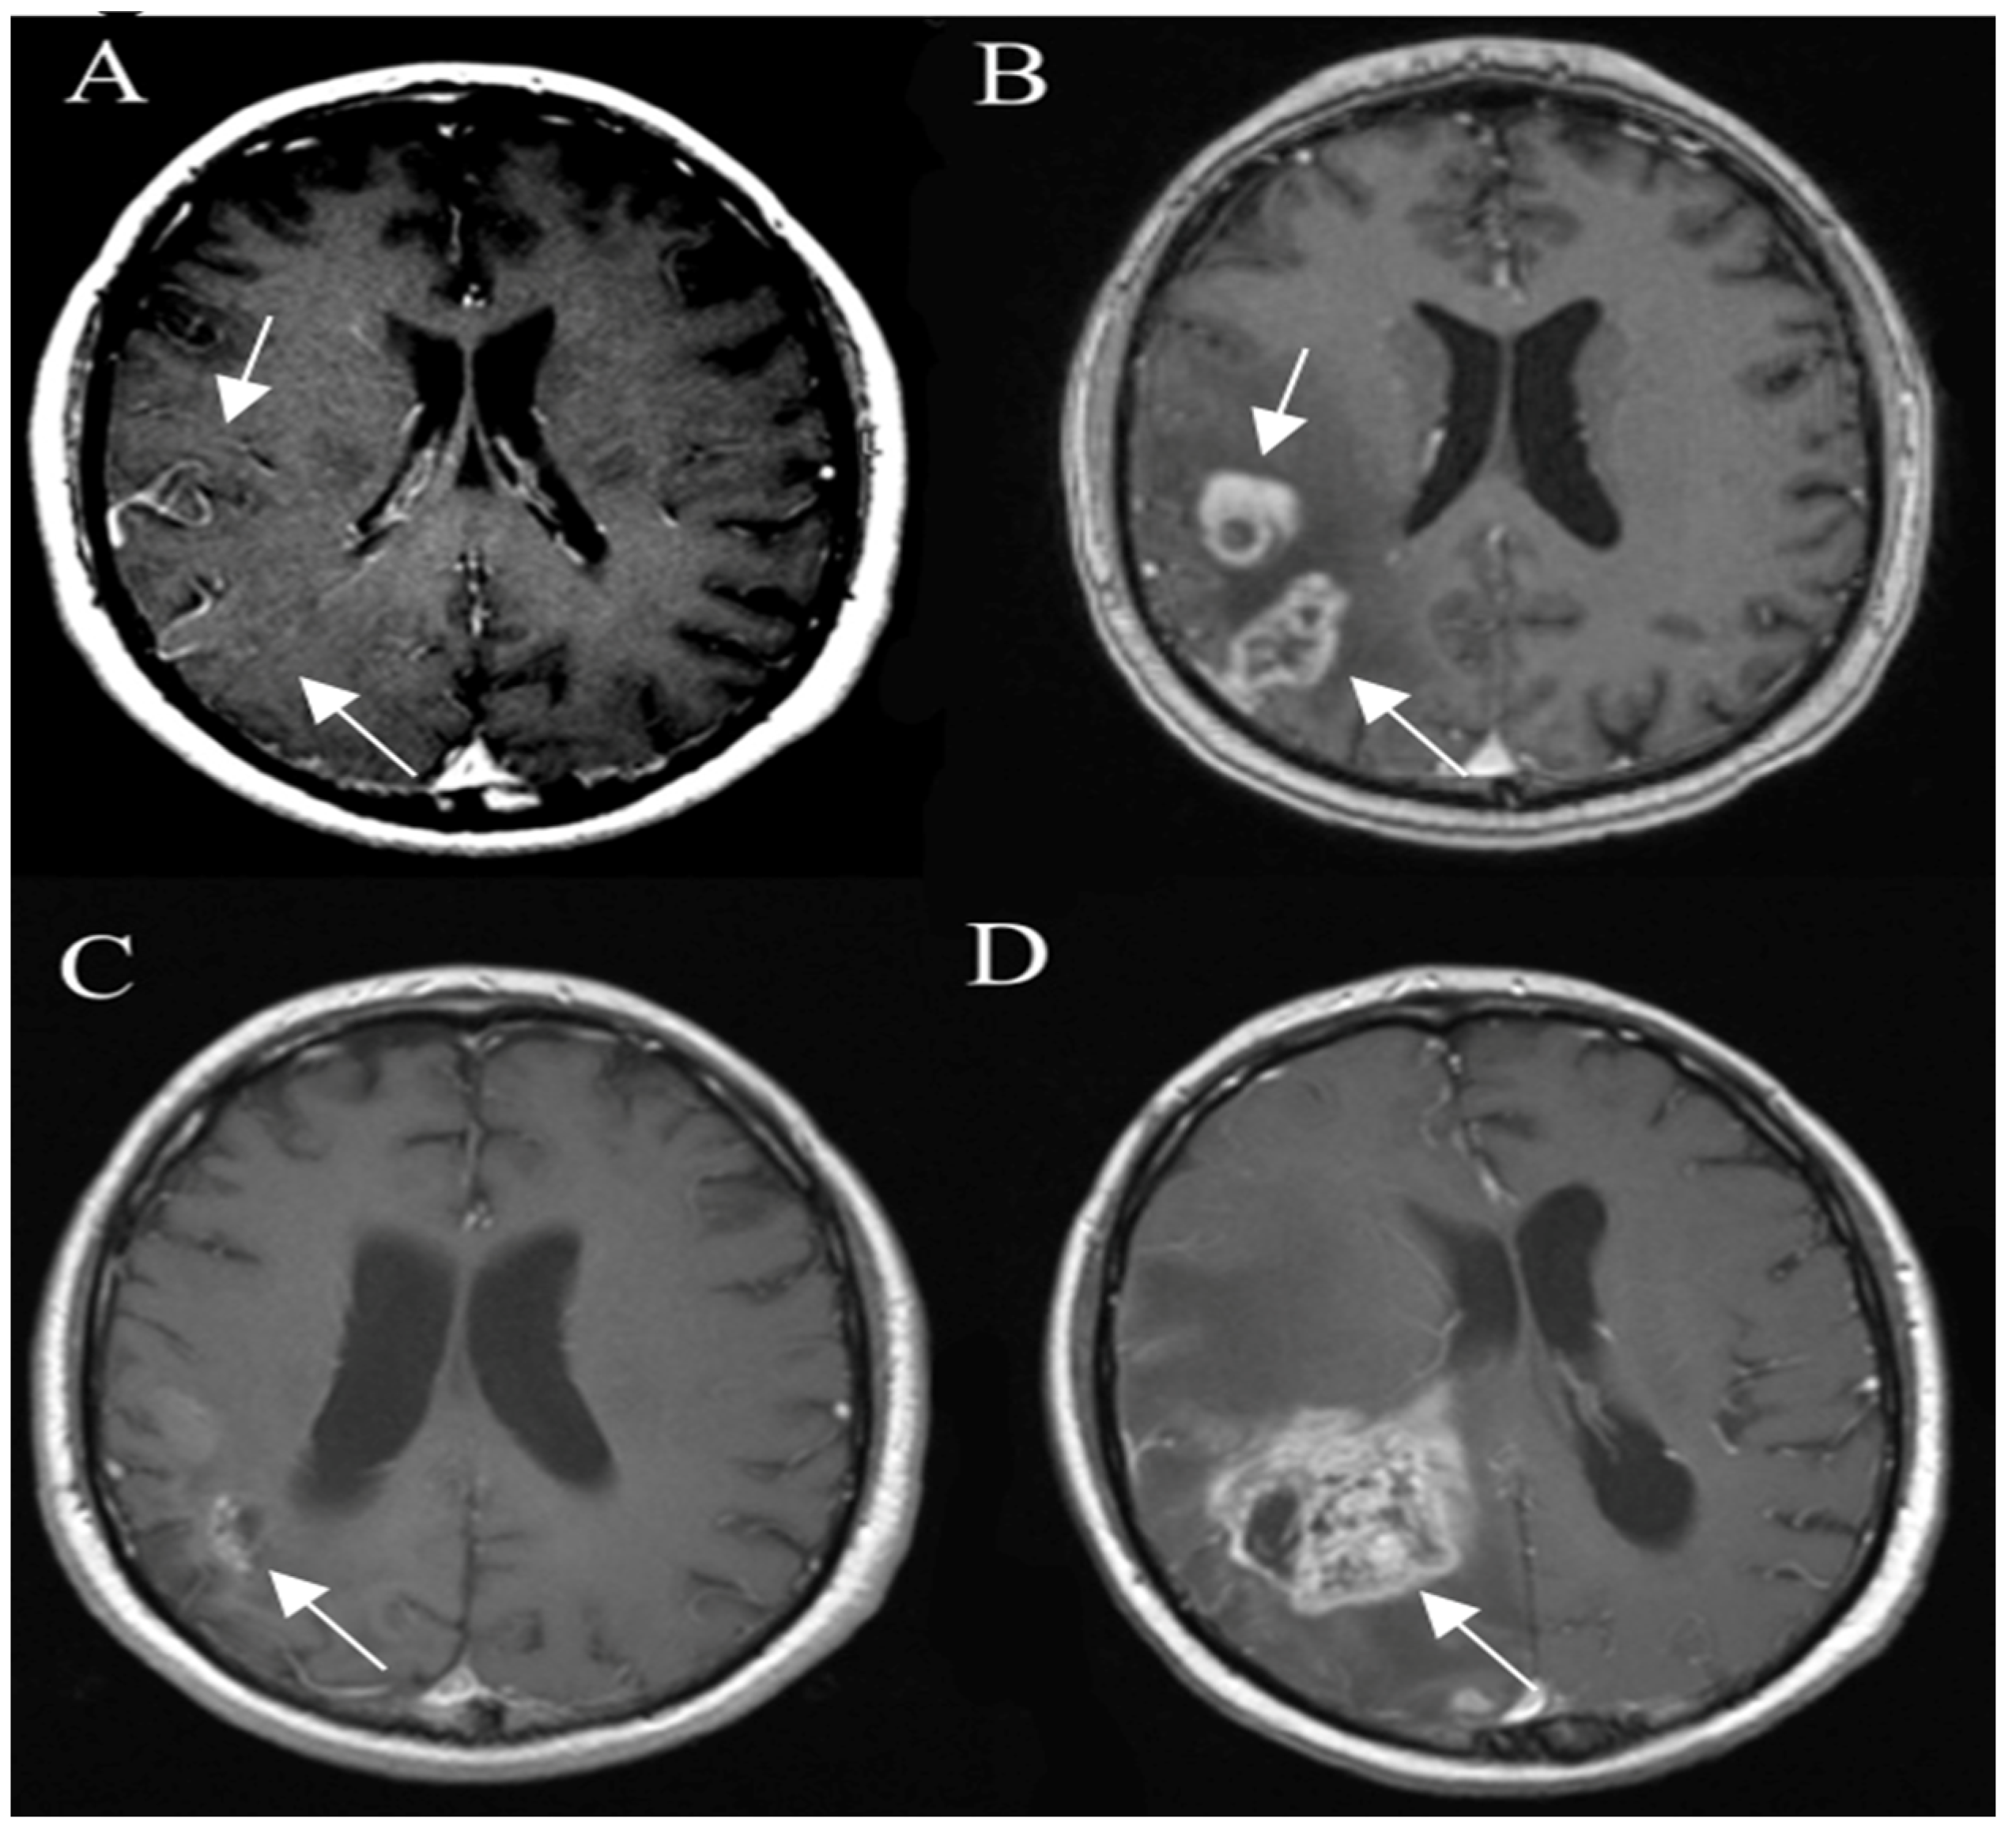

3.6. Posttreatment Imaging

3.6.1. True Progression

3.6.2. Pseudoprogression

3.6.3. Pseudoresponse

3.6.4. Radiation Necrosis